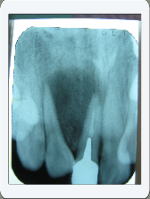

<症例 1> 根管治療

治療前 治療後

黒いおおきな影 膿の袋 が消えています。膿の袋の広が

りによって歯まで押し広げられていました。しかし根管治

療によって骨が再生して来るとともに歯並びも元に戻って

来ています。

この歯の治療には1年半ぐらいかかりました。

治療を始めた当初は膿がとまらず、非常に困難でした。

しかし治療後は根尖の大きな膿の袋はきれいになりました。

患者様もあきらめずに頑張って通って下さいました。